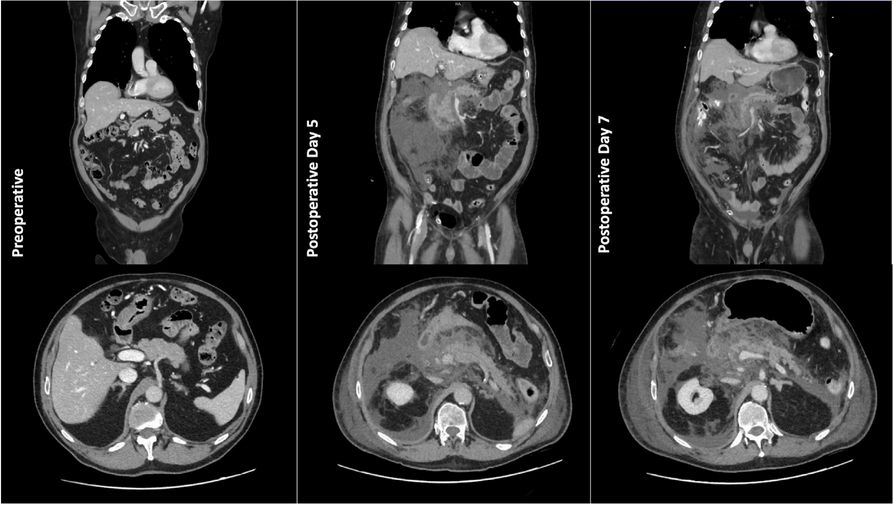

A few hours after the admission in ICU he reported a blunt abdominal pain, mainly on the right side, nausea and the exams showed increased amylase levels, urologists excluded any surgical involvement of pancreatic tissue and suspected a transient sphincter of Oddi dysfunction [3]. After one night in ICU he was transferred to the urology ward due to his clinical stability, even though Amylase peaked at 2340 U/l. Two days later abdominal pain increased to severe, with characteristics of peritonism and increased inflammatory markers. An abdomen-thorax CT scan revealed acute pancreatitis (AP) (Figure 1) and he was transferred to ICU. He started a standard treatment for acute pancreatitis and antibiotic therapy [4].

Fig. 1 (abstract A21).

See text for description